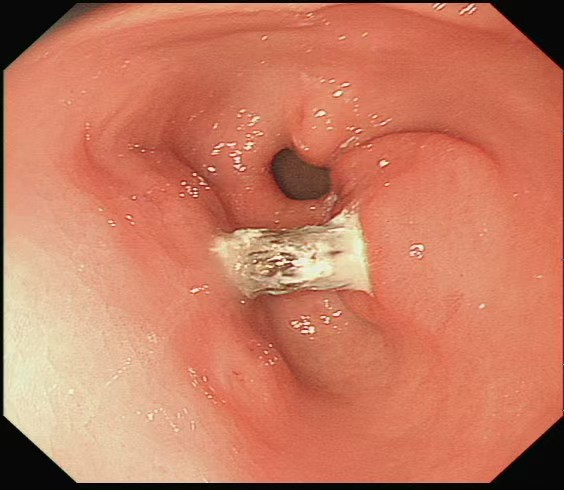

60 岁的赵大娘(化名)被腹痛困扰整整一个月,起初误以为是老胃病复发未重视,直到疼痛难忍才前往湖北科技学院附属第二医院就诊。令人震惊的是,胃镜检查显示,一枚枣核如刀片般横卡在她的胃窦处,两端锋利尖端已深深扎入胃壁,形成穿透性溃疡,甚至将胃的前后壁紧紧 “粘连”,情况危急。

“这枚枣核就像一颗‘定时炸弹’。” 医院消化内科主任高新生介绍,由于枣核在胃内存留时间较长,已与周围组织粘连,取出过程中稍有不慎就可能造成二次损伤,还可能引发更严重的胃穿孔、腹膜炎,直接危及生命。

面对危急情况,高新生主任团队凭借丰富的临床经验和成熟的内镜技术,借助透明帽辅助清晰暴露视野,再用异物网篮精准抓取枣核,成功避开其锋利边缘,将这枚 “致命异物” 完整取出。随后,医生用钛夹如同 “内部缝合针”,牢牢封闭了溃疡创面。经过 5 天的住院观察,赵大娘腹痛症状明显缓解,复查结果正常后顺利出院。